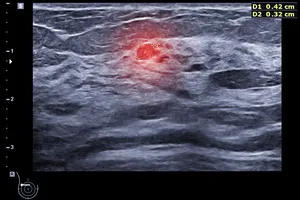

유방 결절은 다양한 원인으로 발생하며, 대부분 양성이지만 일부는 악성일 수 있습니다. 조직검사는 결절의 일부를 채취하여 현미경으로 분석하는 검사입니다.

이를 통해 결절이 양성인지 악성인지, 악성일 경우 어떤 종류의 암인지 정확하게 판단할 수 있습니다. 유방암은 조기에 발견할수록 치료 효과가 좋습니다. 조직검사를 통해 유방암을 조기에 발견하면 완치율을 높일 수 있습니다.

유방 결절 조직검사 방법

세침흡인검사보다 굵은 바늘을 이용하여 결절의 조직을 일정량 채취하는 방법입니다. 장점은 세침흡인검사보다 많은 양의 조직을 얻을 수 있어 진단의 정확도가 높습니다. 단점은 세침흡인검사보다 통증이 약간 더 심할 수 있으며, 출혈이나 감염의 위험이 약간 증가할 수 있습니다.